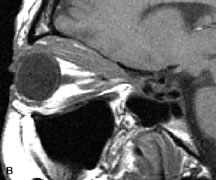

Fig. 16. A-C, T1-weighted MR scans obtained with a high-resolution surface coil demonstrate fusiform enlargement of the extraocular muscles. The medial, lateral, and inferior rectus muscles are especially involved. Note the relative sparing of the tendinous insertions, a finding characteristic of this disease process, as well as fatty infiltration of the lateral and inferior rectus muscles. There is marked proptosis, best visualized on the sagittal image (A), and mild crowding of the optic nerve at the orbital apex.